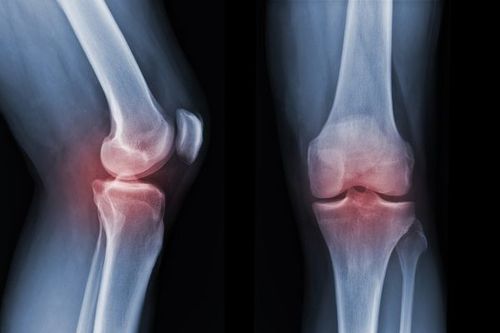

• X‑ray: Used to detect bone fractures, joint dislocation, osteoarthritis, or bone tumour‑related conditions.

X-rays can detect fractures, dislocations, osteoarthritis, bone tumors